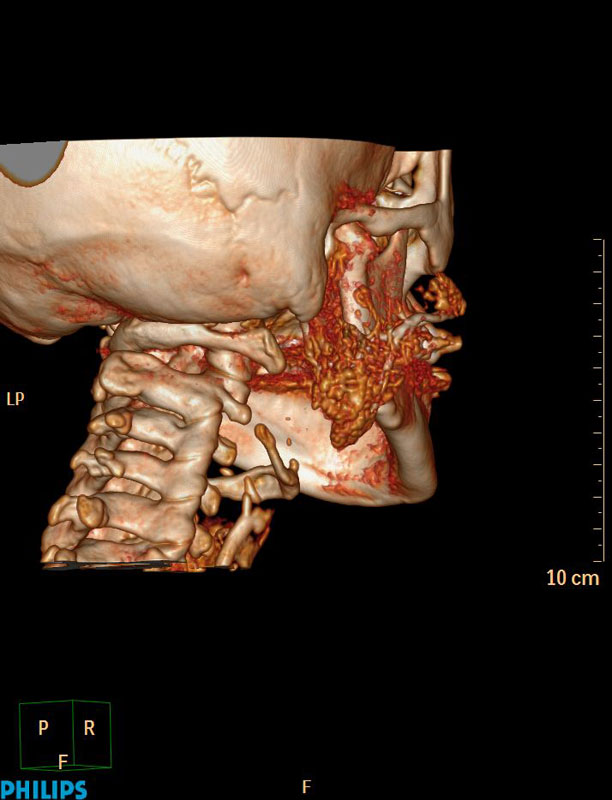

Апробированы современные методики в диагностике заболеваний слюнных желез, которые позволяют с высоким пространственным разрешением и возможностью построения 3D реконструкций оценить наличие нарушения проходимости протоков слюнных желез